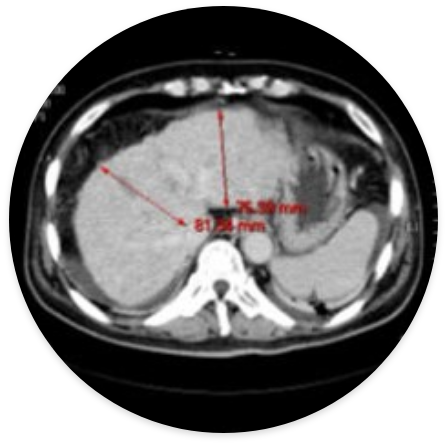

Liver cirrhosis (male 59 years old)-After treatment, hepatocytes are regenerated to increase the size of the liver and soften the liver tissue